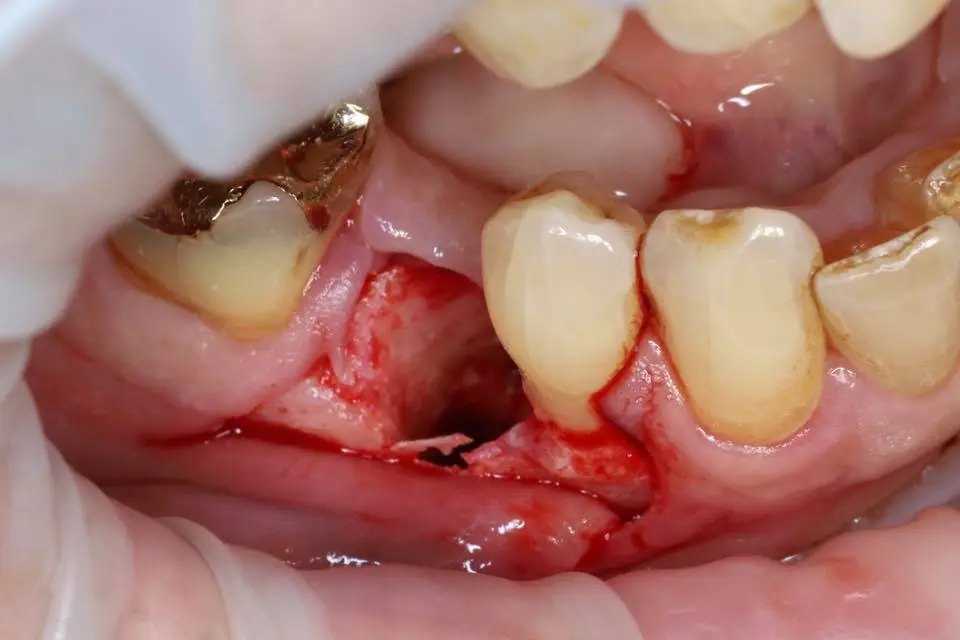

Esityksissä käsitellään materiaalin valmistelua, käyttöä luusiirteissä sekä kliinisiä tuloksia, kuten nopeaa luunmuodostusta (jopa 50 % uutta luuta 12 viikossa), ilman tarvetta erilliselle kollageenikalvolle.

This lecture will explore how surgical simplicity combined with biologically active materials can achieve outstanding results across a range of indications — from socket preservation and regeneration to sinus lifting. Through clinical cases and practical protocols, Dr. Stuart Kilner will demonstrate how to optimise handling, improve efficiency, and achieve stable regeneration by working with, not against, the body’s innate capacity to heal.

EthOss cases by Dr Stuart Kilner